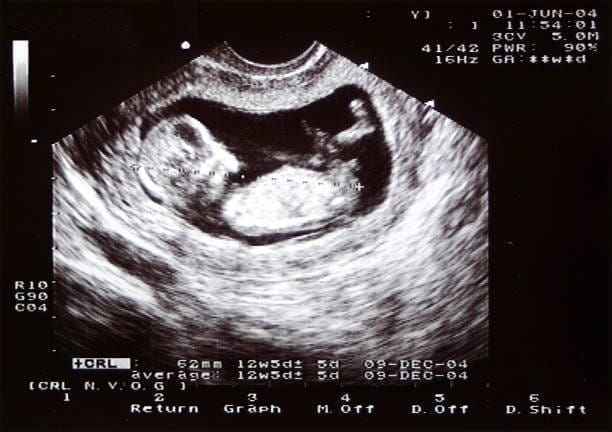

2D Ultrasounds

2D ultrasounds offer black-and-white images that provide essential views of the baby’s internal structure. Ideal for assessing fetal health, these images are clear but flat, focusing on anatomical details.

2D Ultrasounds remain the gold standard for medical diagnostics in prenatal care, as they are crucial for evaluating fetal development, detecting potential issues, and monitoring the pregnancy’s progress

Furthermore, 2D ultrasounds are instrumental in routine checks, such as measuring the fetus’ size, assessing the placental location, and evaluating the amniotic fluid levels.

Their reliability and precision in providing essential details make them indispensable for obstetricians and gynecologists.